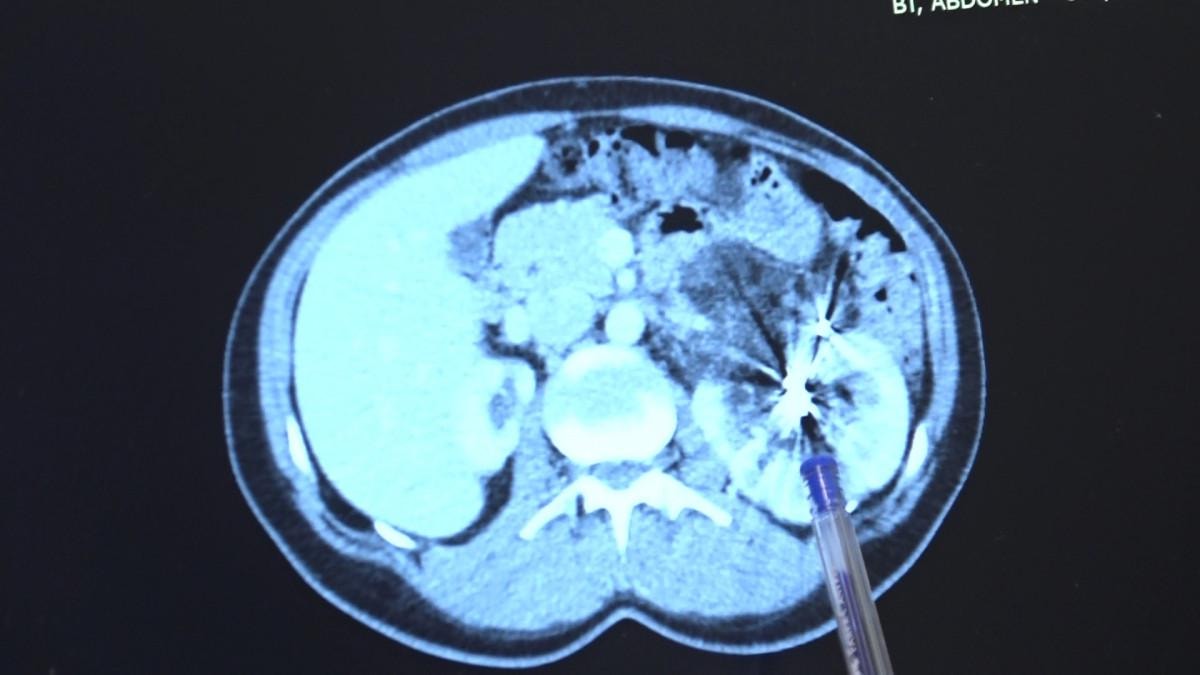

Yıllar sonra tekrar MR çektiren hastanın tek böbreğinde bu sefer bir kitle olduğu görüldü.

Zorlu bir ameliyatı başarıyla tamamlayan Bursa Medicana Hastanesi Üroloji Uzmanı Doç. Dr. Ahmet Şahan, hastanın durumunun şuan iyi olduğunu belirterek, “Nurcan Hanım 35 yaşında bize İzmir'den geldi. Doğuştan tek böbrekli bir böbreği küçük olduğu için işlevsiz durumda. Sağlam böbreğinde ise 2016'da tanısı konmuş giderek büyüyen iyi huylu "anjiomyolipomu" denilen 12 santimetre boyutunda bir kitlesi var.

Bu kitle artık böbreğin damarlarını içerisine almış komplike bir kitle durumunda. Hastaya iki kez anjioembolizasyon tedavisi uygulanmış fakat başarısız olduğu için kitle büyümeye devam etmiş. Kadınlarda 4 santimetreden büyük anjiomyolipomular kendiliğinden kanayarak yaşamı tehlike altına attığı için bu kitlelerin alınması gerekiyor.